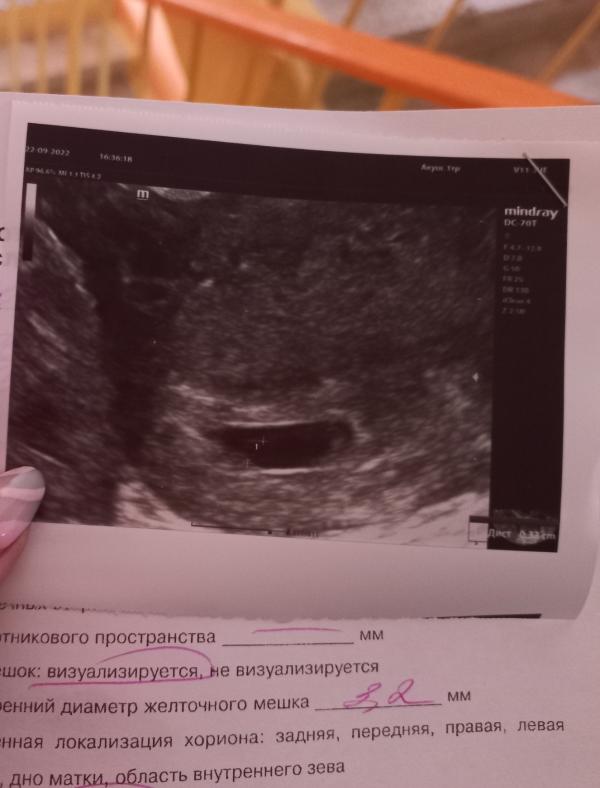

На фото узи от 22.09.